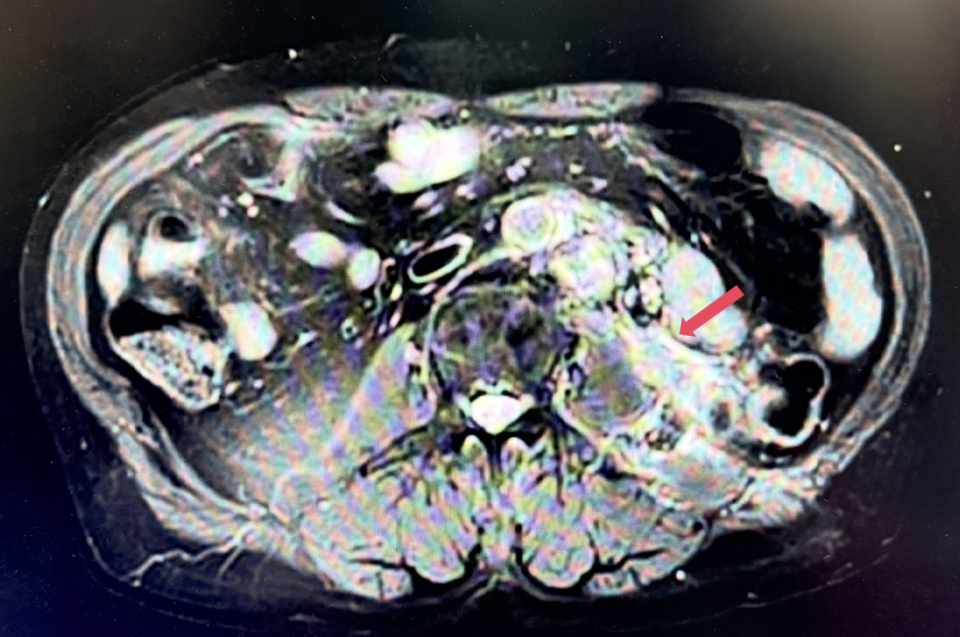

2023年1月,基线